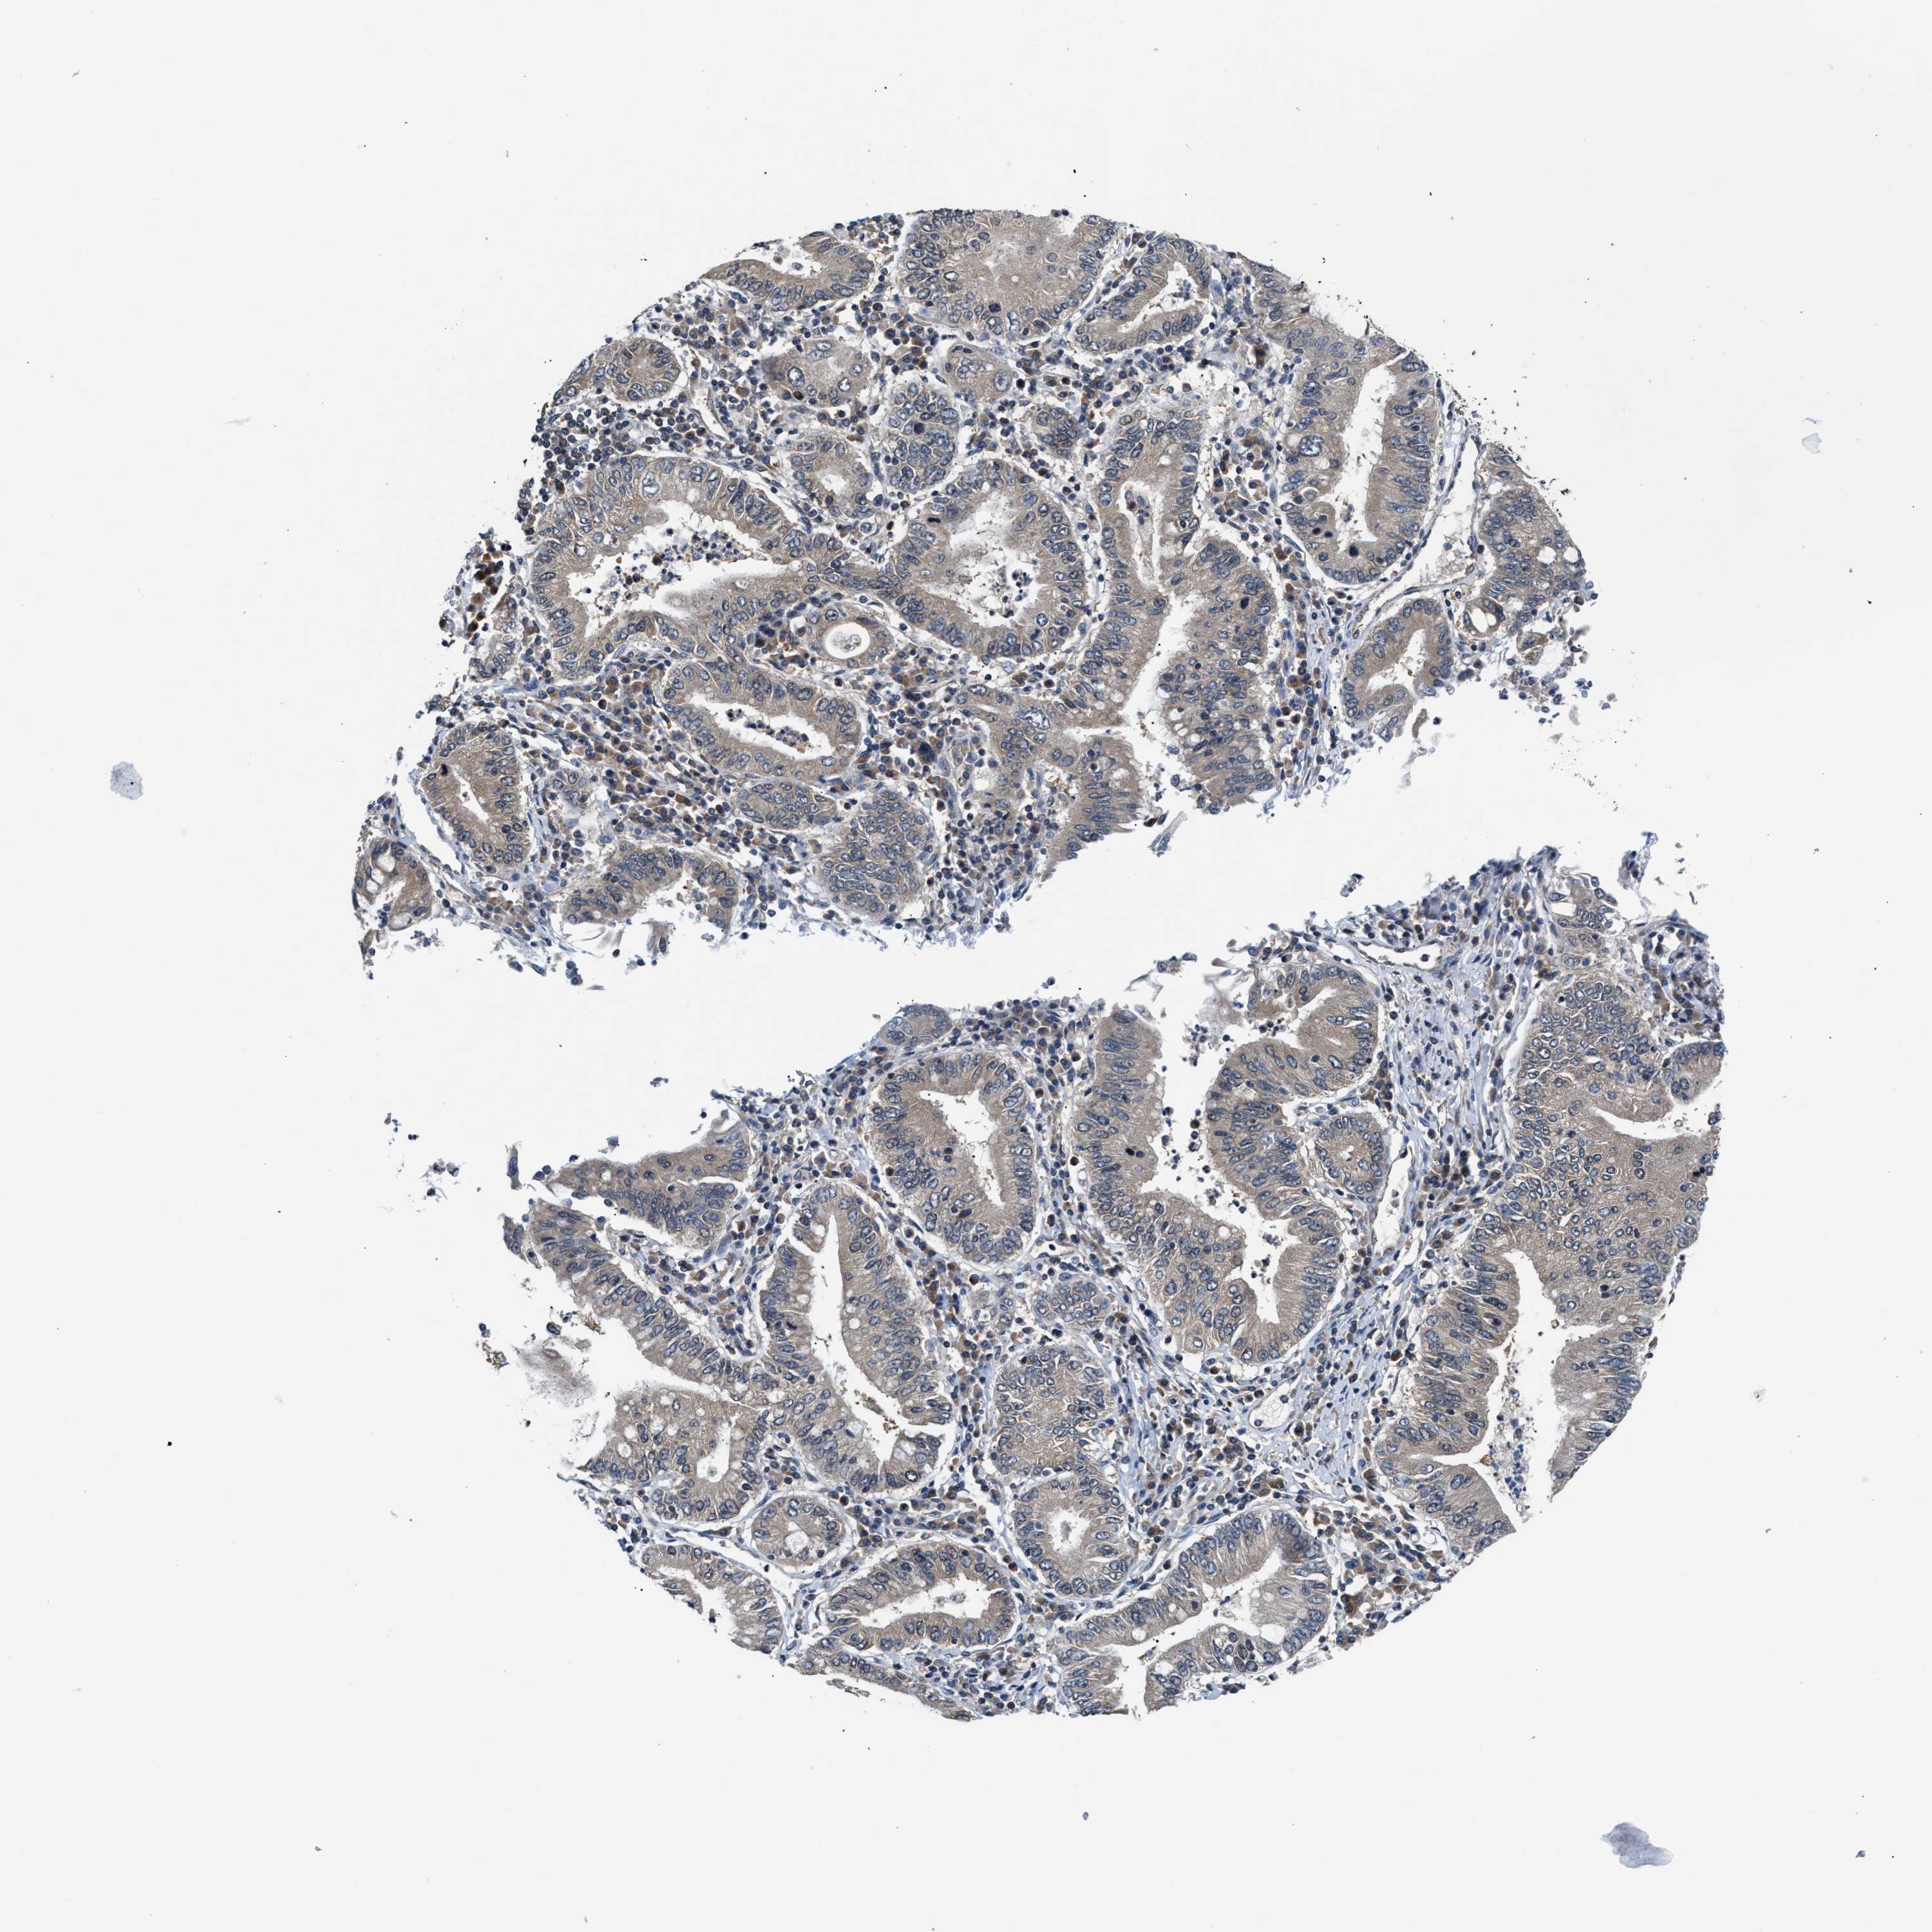

STOMACH CANCER - Protein expressioni

A mouse-over function shows sample information and annotation data. Click on an image to view it in a full screen mode. Samples can be filtered based on level of antibody staining by selecting one or several of the following categories: high, medium, low and not detected. The assay and annotation is described here.

Note that samples used for immunohistochemistry by the Human Protein Atlas do not correspond to samples in the TCGA dataset.

Antibody stainingi

Antibody staining in the annotated cell types in the current human tissue is reported as not detected, low, medium, or high, based on conventional immunohistochemistry profiling in selected tissues. This score is based on the combination of the staining intensity and fraction of stained cells.

Each image is clickable and will lead to virtual microscopy that enables deeper exploration of all samples and also displays staining intensity scores, fraction scores and subcellular localization as well as patient and tissue information for each sample.

Antibody HPA026303

Antibody CAB020822

Staining

High

Medium

Low

Not detected

Intensity

Strong

Moderate

Weak

Negative

Quantity

>75%

75%-25%

<25%

None

Location

Nuclear

Cytoplasmic/membranous

Cytoplasmic/membranous,nuclear

Adenocarcinoma, NOS

Adenocarcinoma, High grade